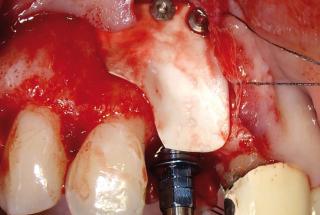

Clinical cases

MPI closely monitors clinical cases in the market to ensure their correct functioning and successful outcome.